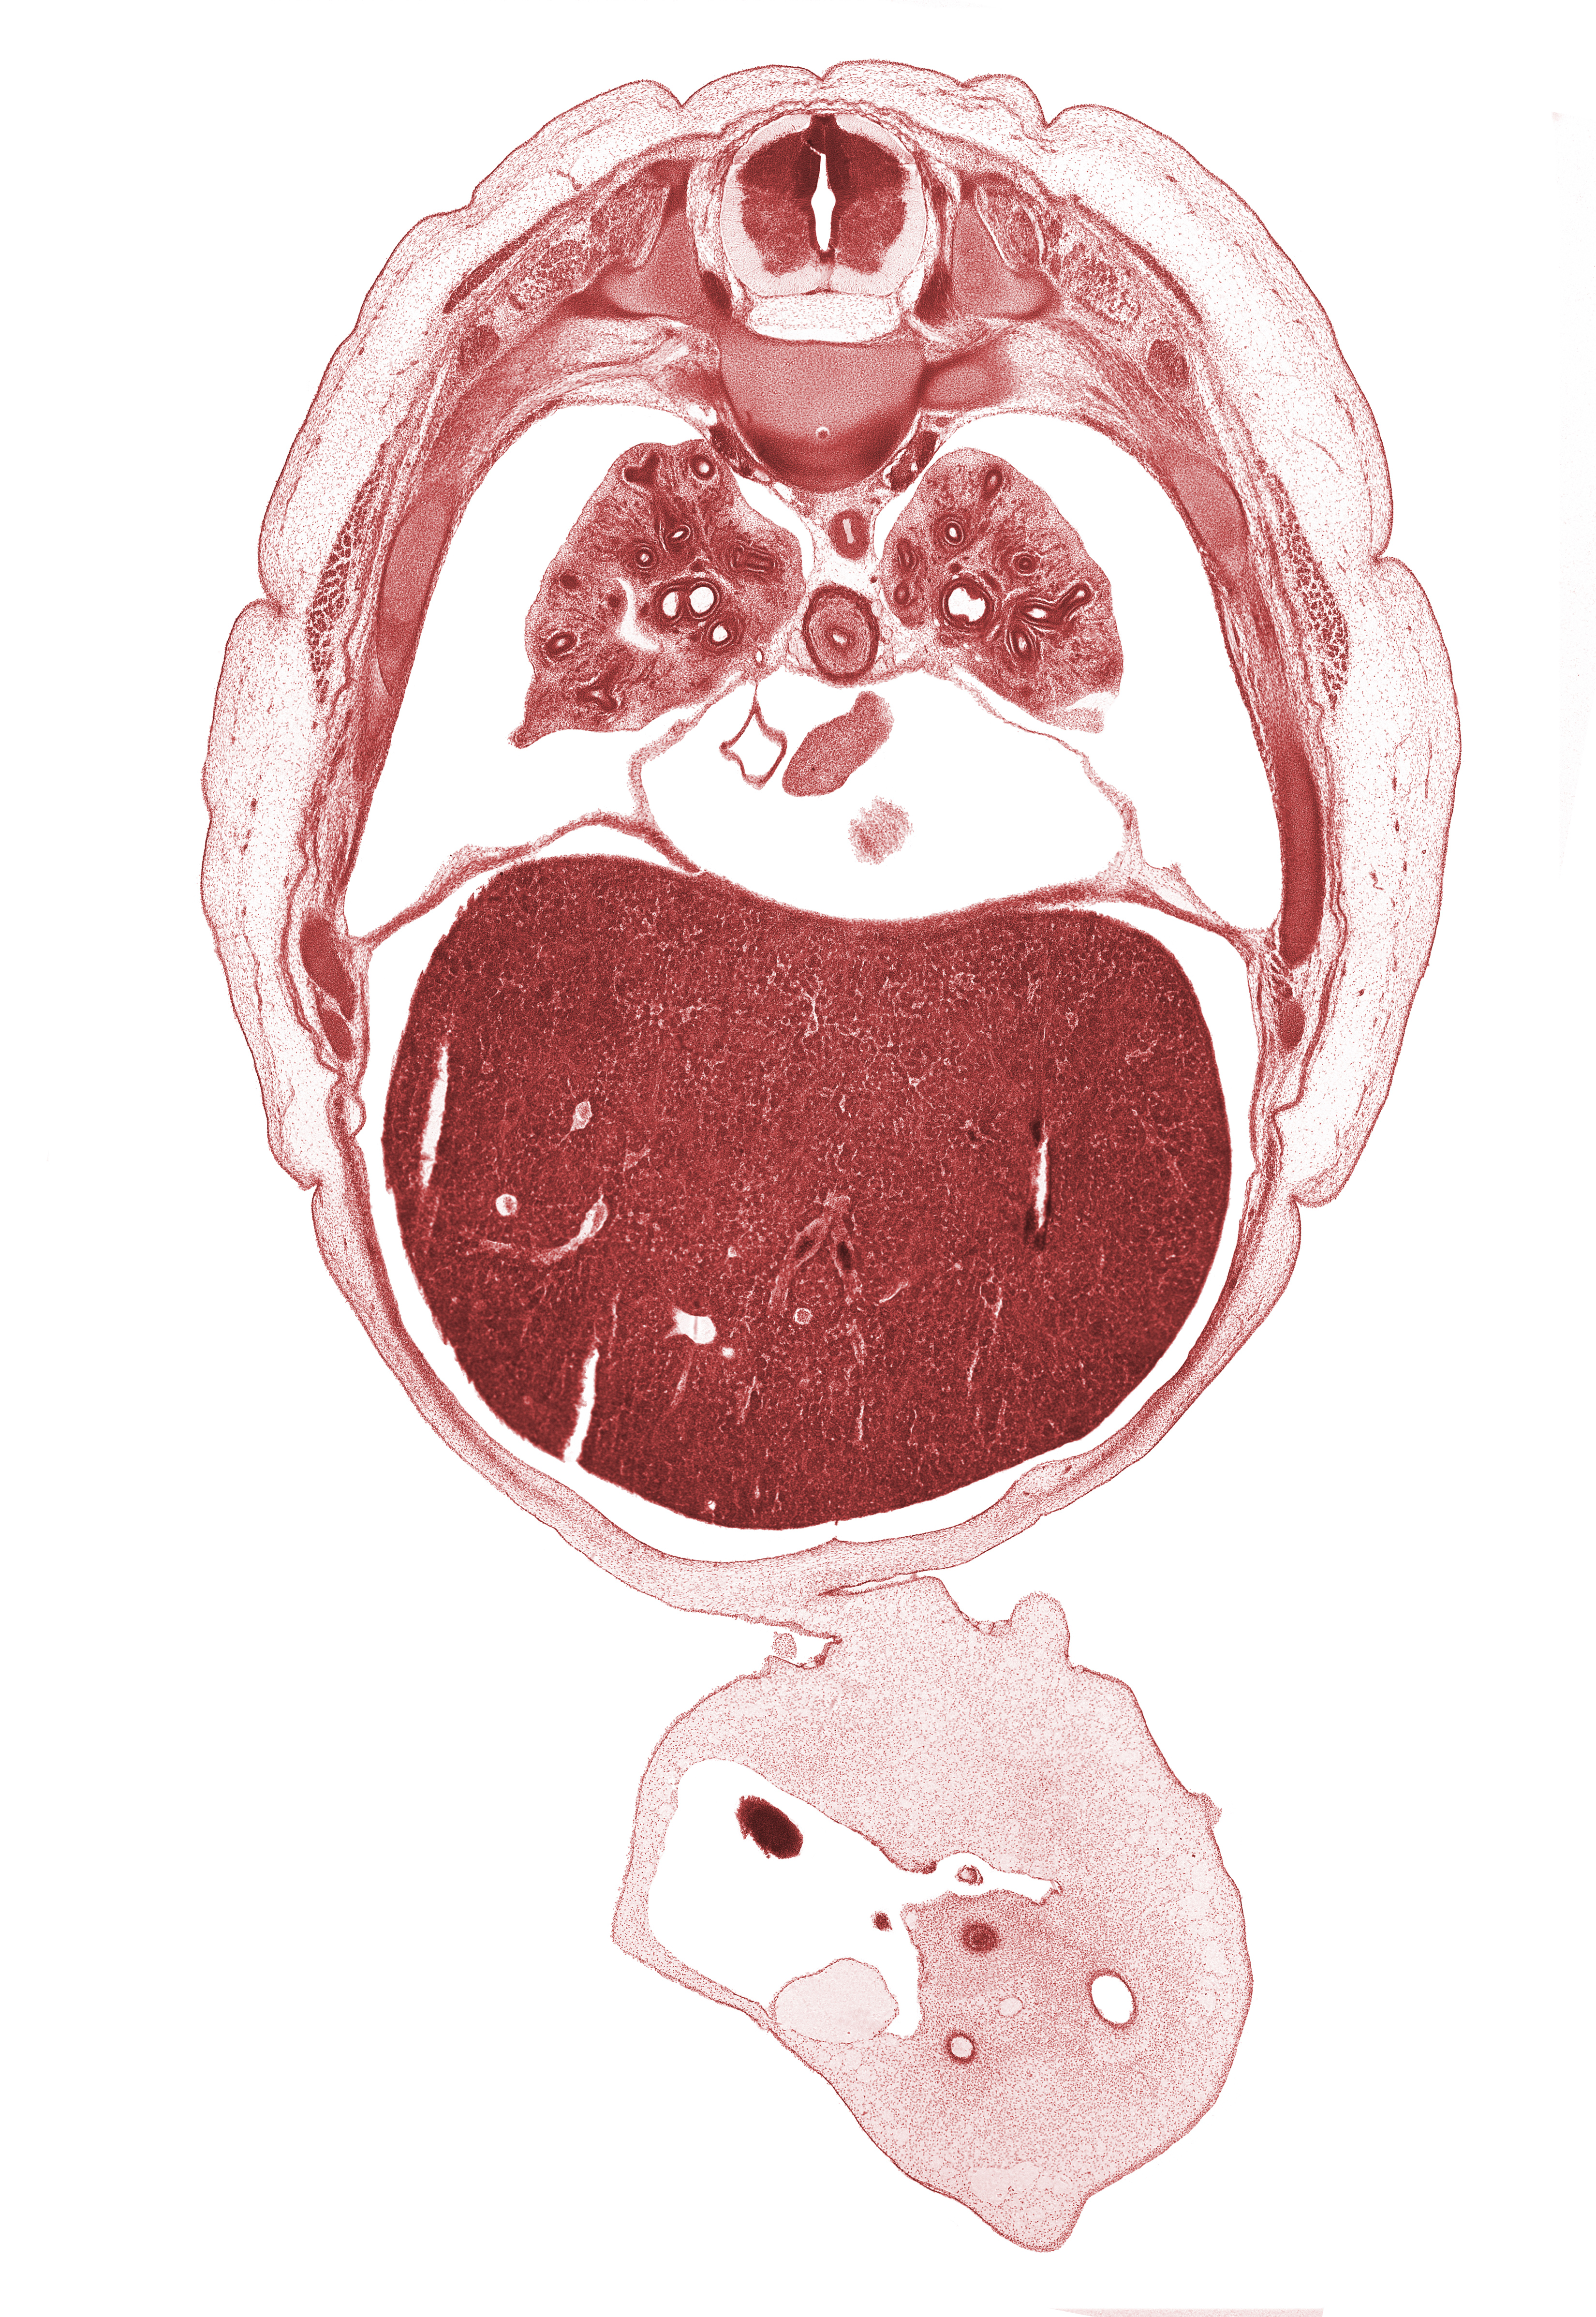

S-1 spinal nerve, T-6 spinal ganglion, allantois, artifact separation(s), caudal edge of left ventricle, caudal edge of right atrium, central tendon of diaphragm, edge of herniated midgut, head of rib 7, inferior vena cava, junction of abdominal wall and umbilical cord, left lobe of liver, left umbilical artery, lower lobe of left lung, lower lobe of right lung, lower secondary bronchus, muscular part of diaphragm, pericardial cavity, peritoneal cavity, pleural cavity, right lobe of liver, right lower pulmonary vein, right umbilical artery, sympathetic trunk, umbilical vein

Carnegie Embryo #4090   |   Location: 18-3

Keywords: S-1 spinal nerve, T-6 spinal ganglion, allantois, artifact separation(s), caudal edge of left ventricle, caudal edge of right atrium, central tendon of diaphragm, edge of herniated midgut, head of rib 7, inferior vena cava, junction of abdominal wall and umbilical cord, left lobe of liver, left umbilical artery, lower lobe of left lung, lower lobe of right lung, lower secondary bronchus, muscular part of diaphragm, pericardial cavity, peritoneal cavity, pleural cavity, right lobe of liver, right lower pulmonary vein, right umbilical artery, sympathetic trunk, umbilical vein